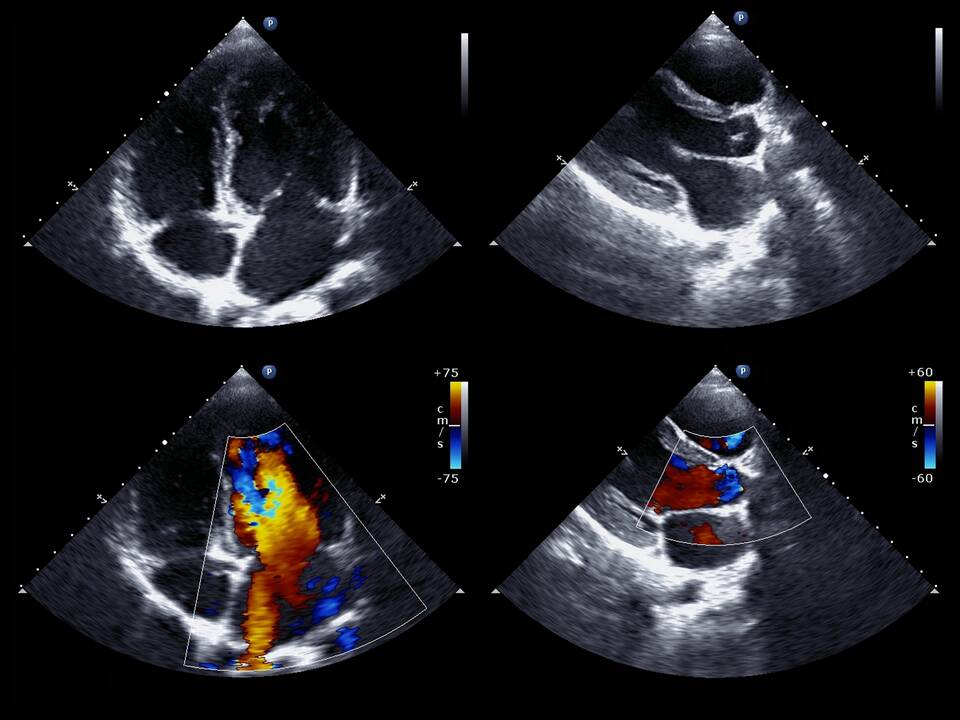

Фракция выброса (ФВ) 60%, выявленная при ультразвуковом исследовании сердца, является важным показателем сердечной функции. Рассмотрим его значение и клиническую интерпретацию.

Что такое фракция выброса

- Количественный показатель насосной функции сердца

- Отношение ударного объема к конечно-диастолическому объему левого желудочка

- Выражается в процентах

- Основной параметр оценки систолической функции

Значение ФВ 60%

- Находится в пределах нормальных значений

- Указывает на хорошую сократительную способность миокарда

- Свидетельствует об отсутствии значимой систолической дисфункции

- Не исключает наличие других сердечных патологий